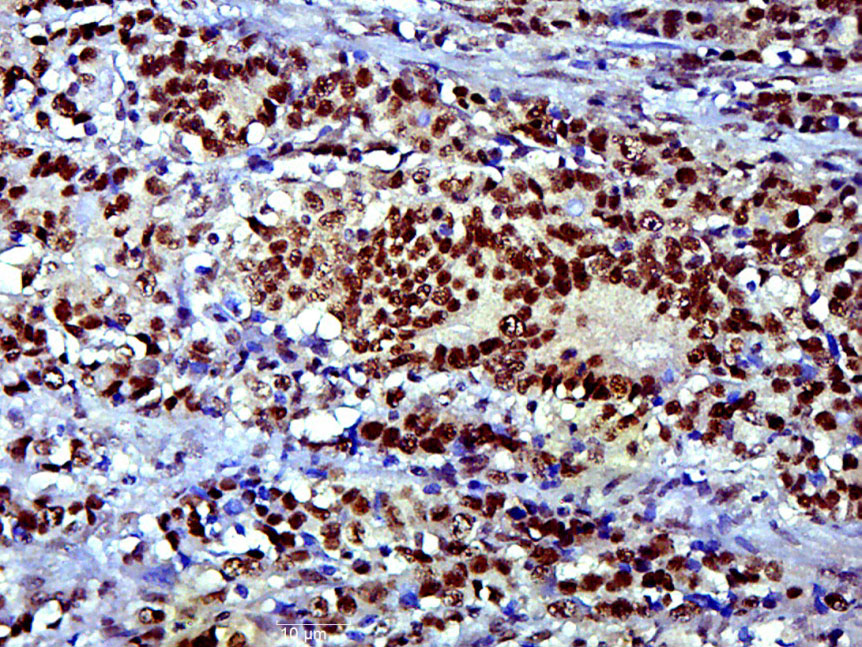

Paraformaldehyde-fixed, paraffin embedded Human colon cancer; Antigen retrieval by boiling in sodium citrate buffer (pH6.0) for 15min; Block endogenous peroxidase by 3% hydrogen peroxide for 20 minutes; Blocking buffer (normal goat serum) at 37°C for 30min; Antibody incubation with SOX9 Polyclonal Antibody, Unconjugated (bs-10725R) at 1:400 overnight at 4°C, DAB staining.

ApplicationsFlow Cytometry, ImmunoFluorescence, Western Blot, ELISA, ImmunoCytoChemistry, ImmunoHistoChemistry, ImmunoHistoChemistry Frozen, ImmunoHistoChemistry Paraffin

- Applications SupplierWB(1:300-5000), ELISA(1:500-1000), FCM(1:20-100), IHC-P(1:200-400), IHC-F(1:100-500), IF(IHC-P)(1:50-200), IF(IHC-F)(1:50-200), IF(ICC)(1:50-200)